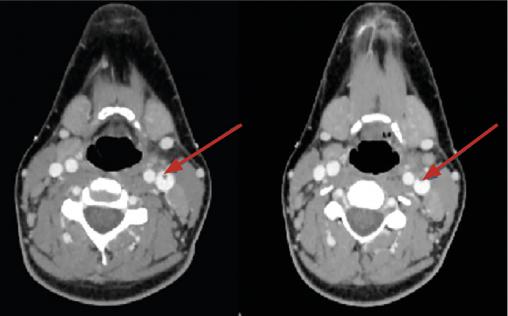

Le scanner cervico-thoracique (fig. 1 et 2 ) montre une thrombose de la veine jugulaire interne gauche ainsi qu’un épanchement pleural bilatéral et une pneumopathie des deux côtés sur emboles septiques, permettant de poser le diagnostic de syndrome de Lemierre.

Le scanner cervico-thoracique (

L’aspect radiologique typique est celui de notre observation. Les abcès pulmonaires, multiples et disséminés par voie hématogène, sont évocateurs. Ils font rechercher une thrombose jugulaire ou de ses collatérales.